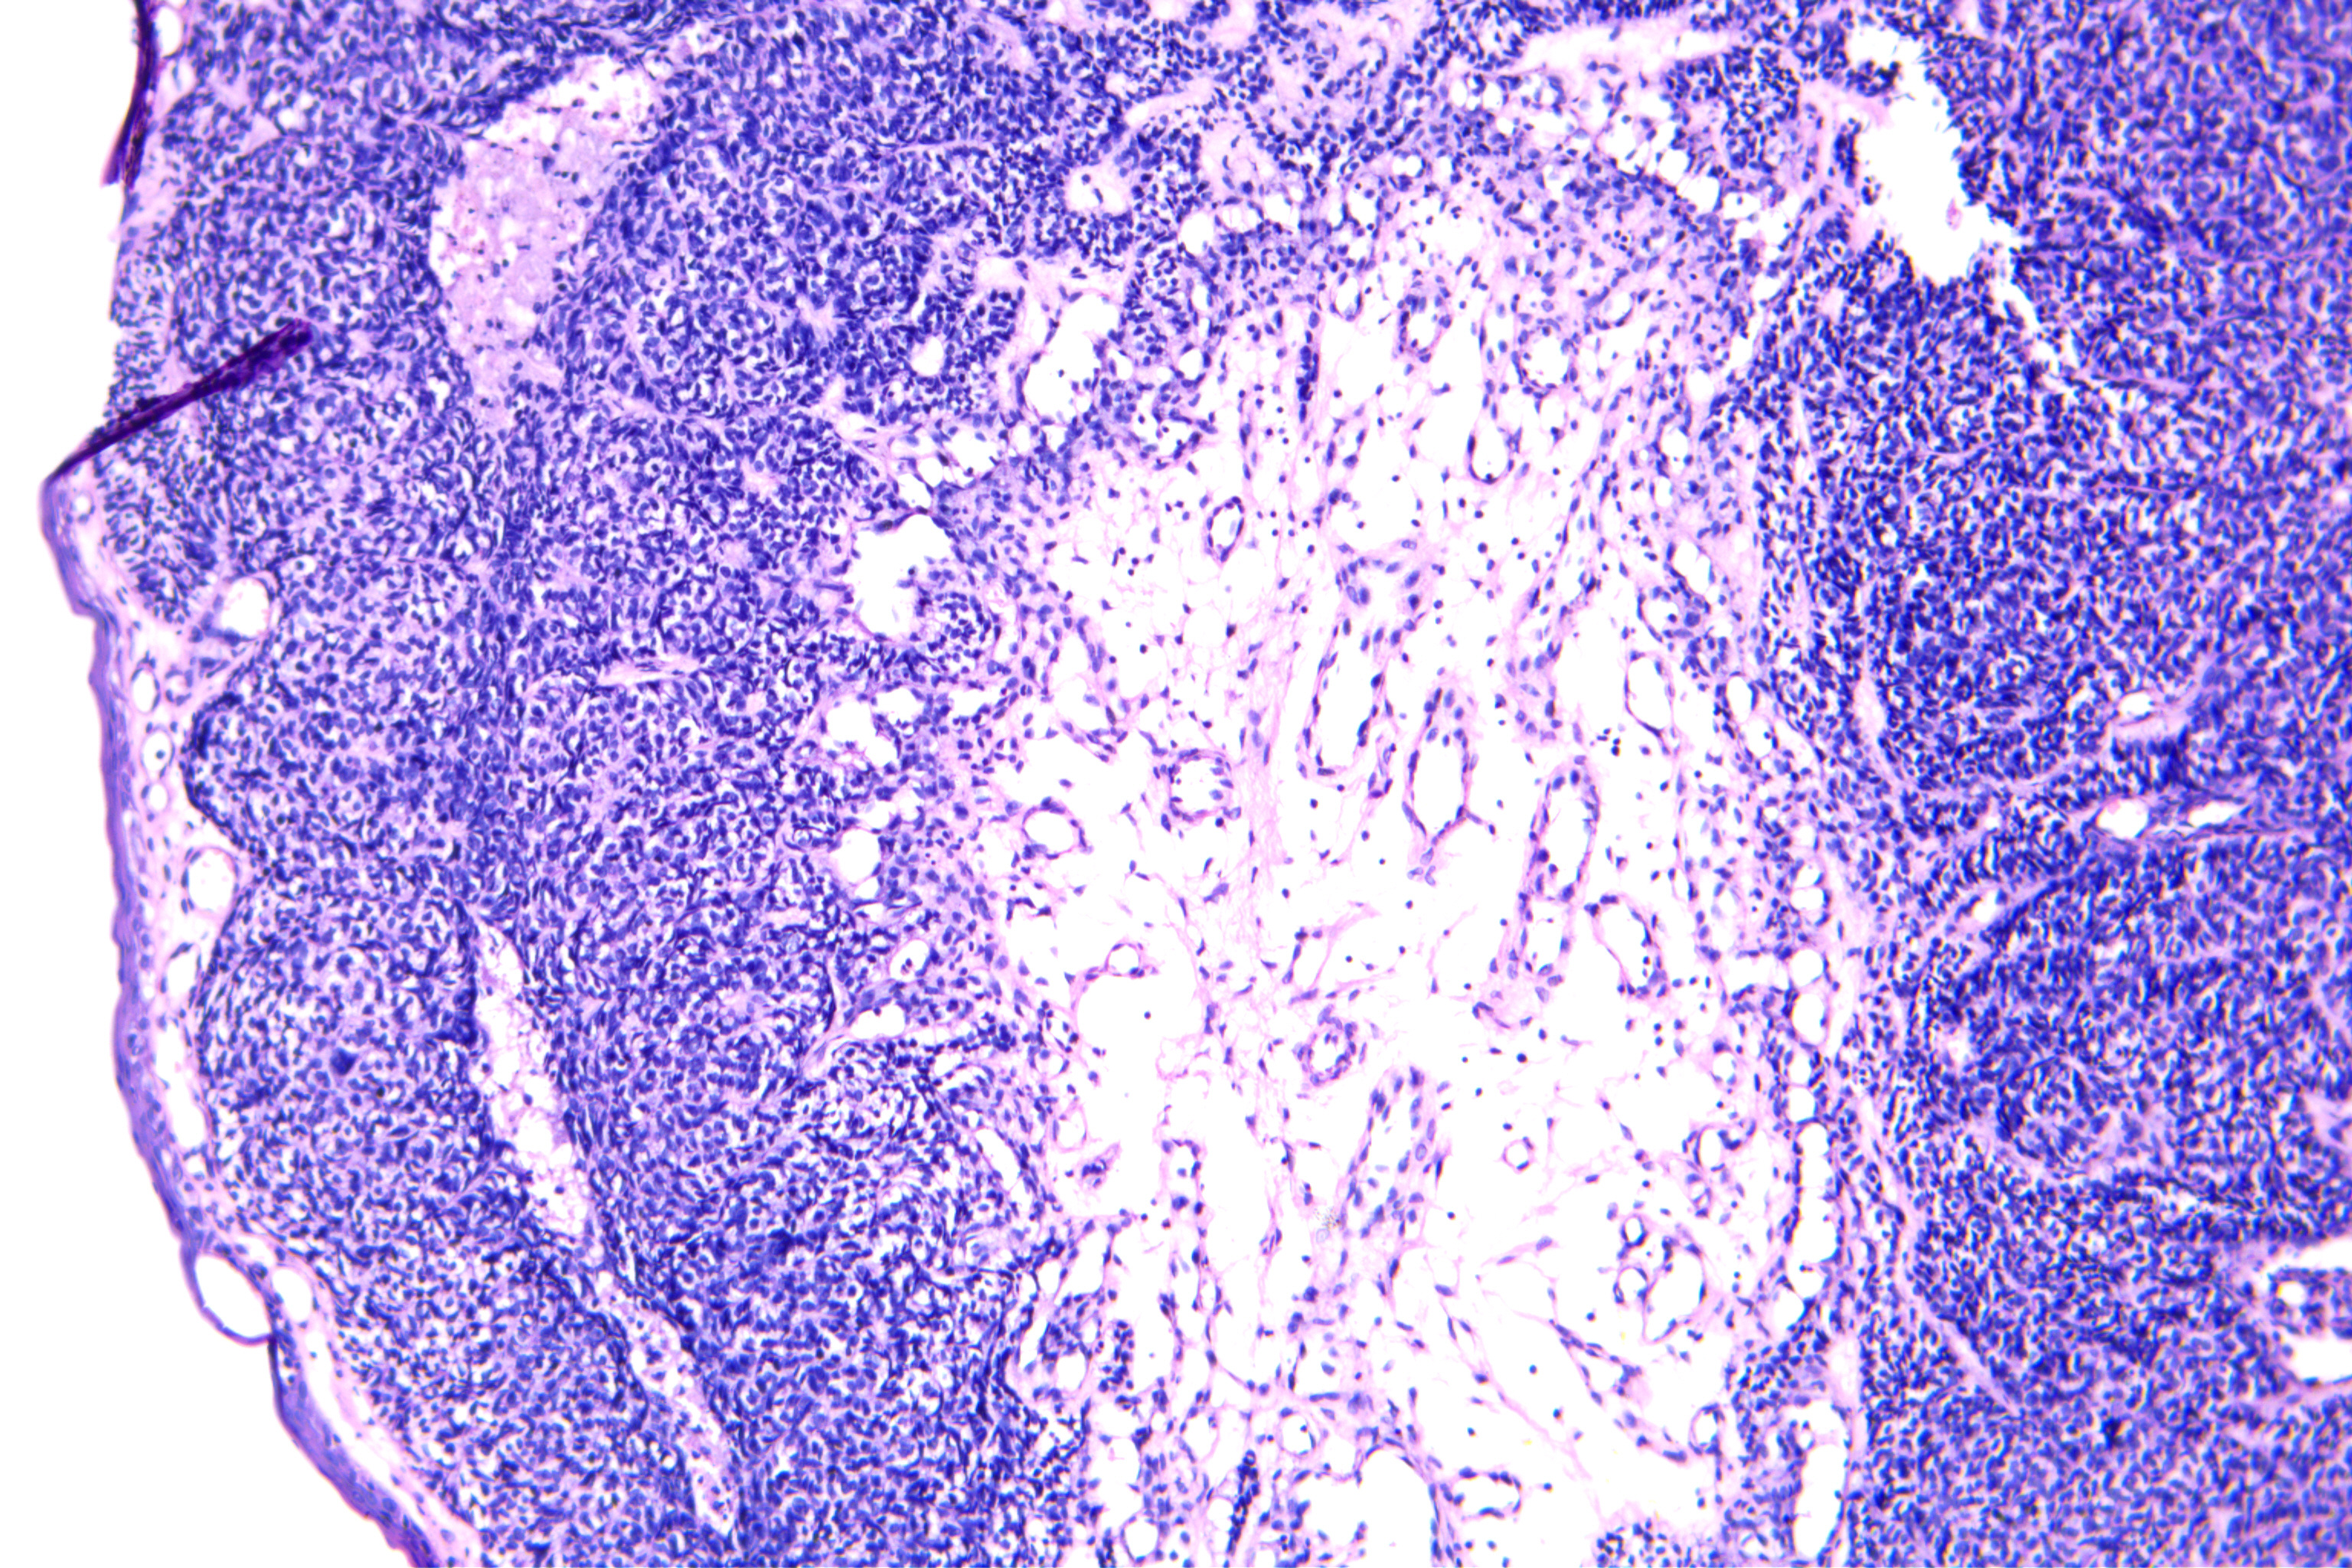

舌下皱褶区粘膜肿块

粘膜下透明、质软、固定的球样肿块,大小直径约0.2cm,表面无破溃。

粘膜组织一块0.5×0.5cm,表面见一突起0.3×0.3×0.2cm,切面灰白色。

Warthin瘤?不是很典型